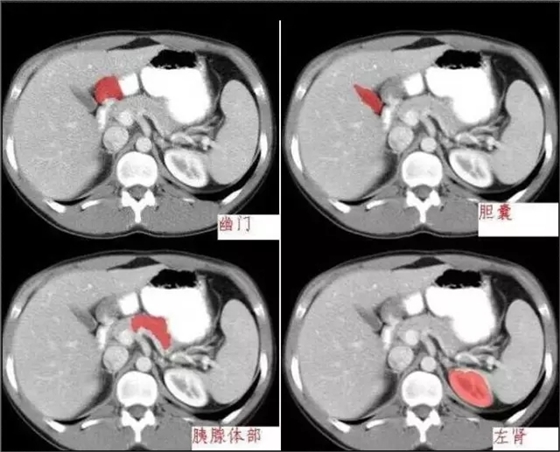

640.webp (11).jpg

640.webp (12).jpg

640.webp (13).jpg

640.webp (14).jpg